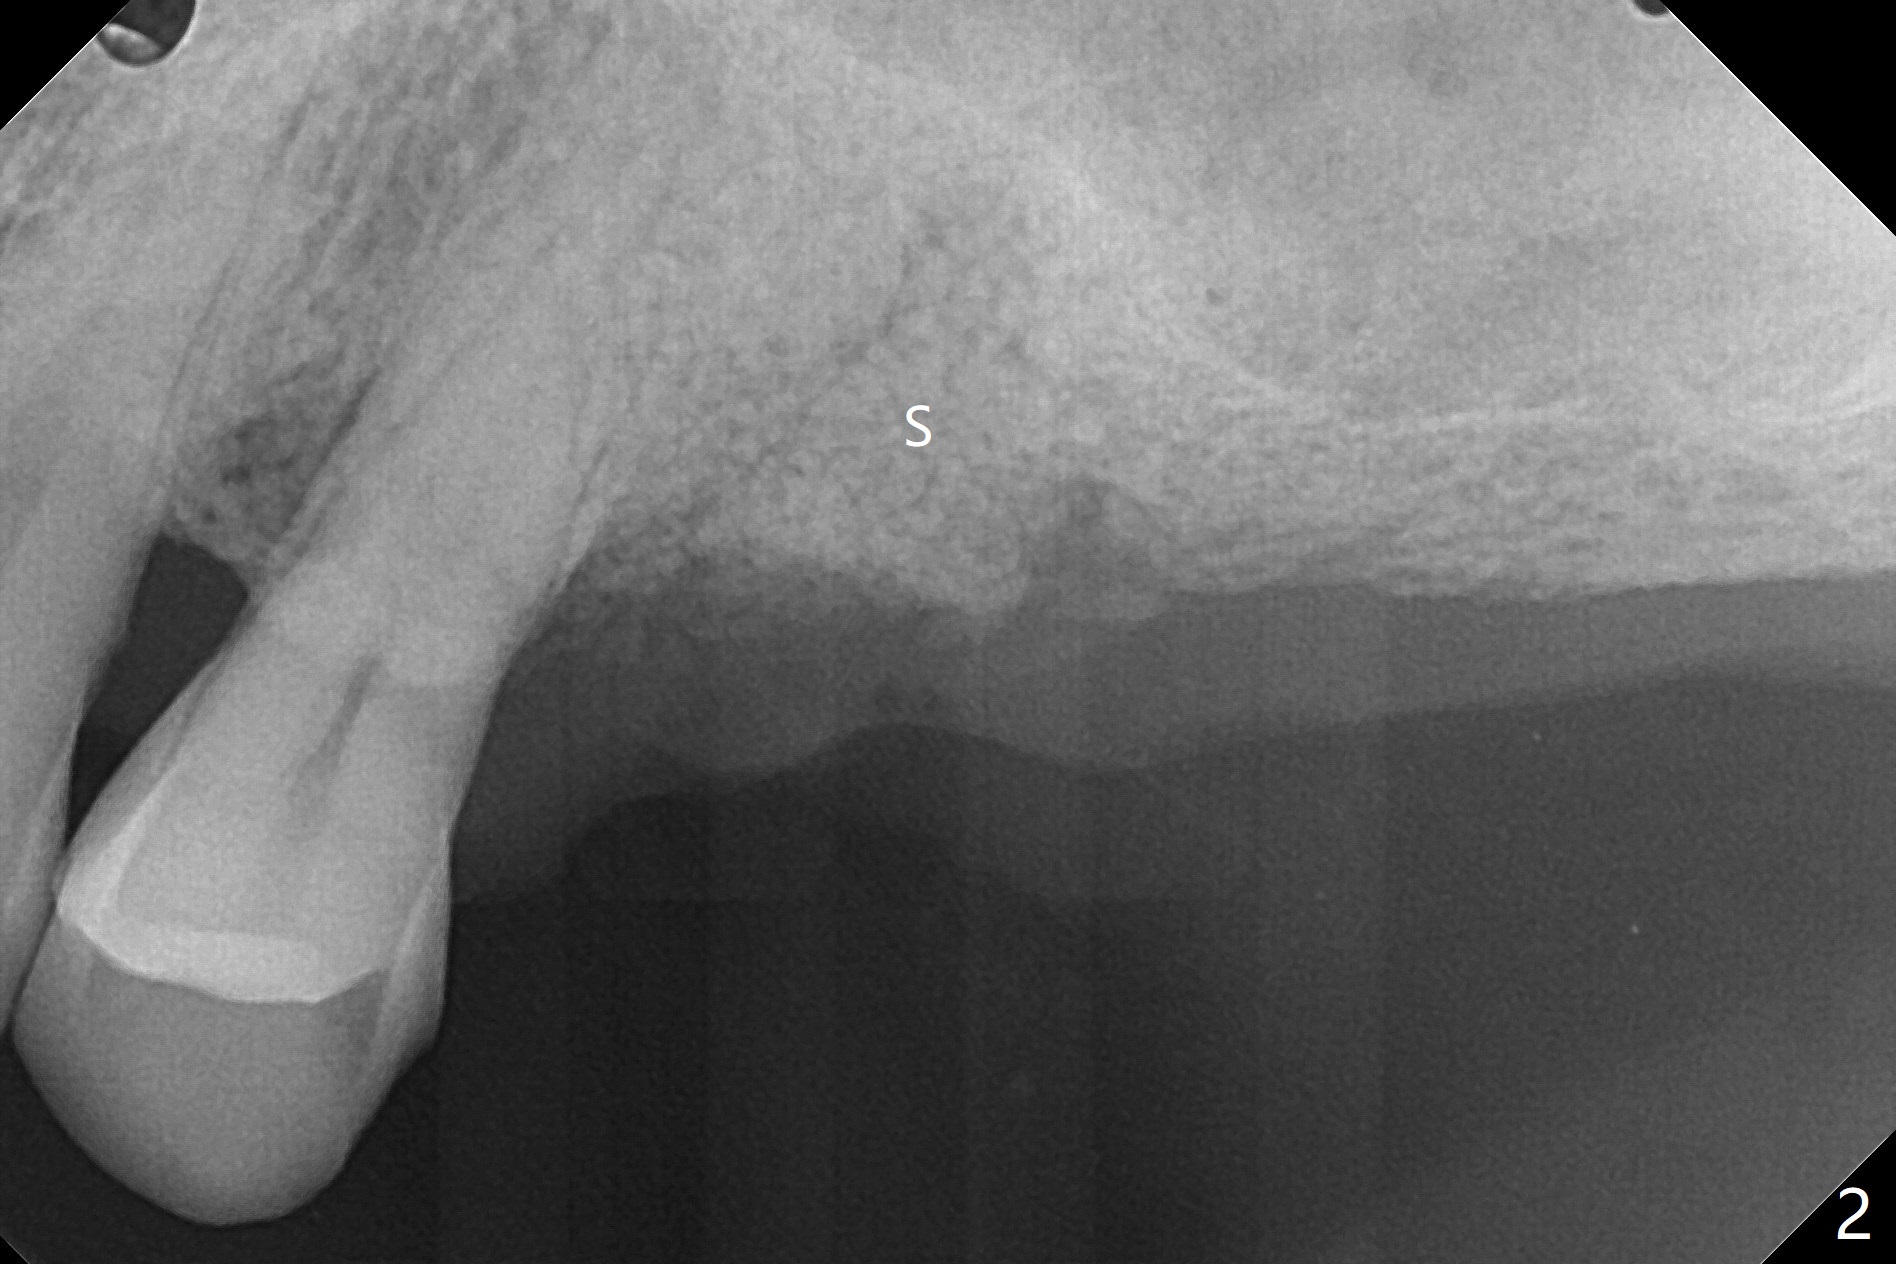

69岁男左上5逆行性(牙周炎导致)牙髓炎(图一)深洗后发展成为不可逆:夜间痛,拔除后植入粘性骨粉(图二:S),将一张PRF膜折叠三层放置牙槽窝开口,使用4-0 PGA缝线,多次figure-8和间断缝合,觉得挺牢靠,就没有使用牙周敷料,后者也估计呆不久。术后严密观察。其实后来伤口愈合正常,但是病人埋怨拔牙造成19号牙疼痛。不过他明天回来拔除30号牙,正好我用完骨粉,但是还有Osteogen Plug和Augma .5 cc 产品, 后者(两者)能维持骨高度吗?